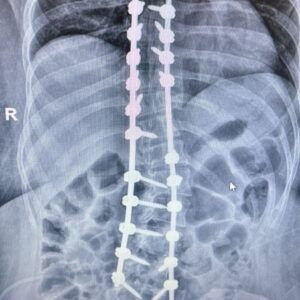

La cirugía, que representa un salto cualitativo respecto a la tradicional cirugía “a cielo abierto”, permite una recuperación más rápida y segura para el paciente. Gracias al uso de un sistema de navegación computarizado, se logró colocar tornillos con mayor precisión y con una exposición significativamente menor a los rayos X.

“En el Hospital Escuela hicimos una intervención con una técnica innovadora con tecnología. A través de la navegación se realiza la colocación de tornillos, lo que mejora la precisión, reduce la exposición a la radiación y permite una mejor corrección de las curvas de la columna”, explicó el Dr. Reble.

La escoliosis en una deformidad en el plano coronal ( frente del paciente ) en forma de S y en algunos casos, implicar rotación vertebral. Si bien no todas las curvaturas generan complicaciones, las más severas pueden provocar dolor, afectar la postura y comprometer funciones de órganos vitales como el corazón, los pulmones y el sistema digestivo.

El tratamiento de la escoliosis depende del grado de curvatura. En casos leves (hasta 25 grados), se realiza un seguimiento expectante. Entre 25 a 40 grados si es esqueléticamente inmadura el paciente se indica el uso de corset. Cuando las curvas superan los 40 grados, como en el caso tratado en el Madariaga, se indica la resolución quirúrgica.

“La escoliosis severa se visualiza a través de radiografías completas de la columna.

Cuando la curvatura supera los 40 grados, evaluamos la intervención quirúrgica”, detalló Reble.